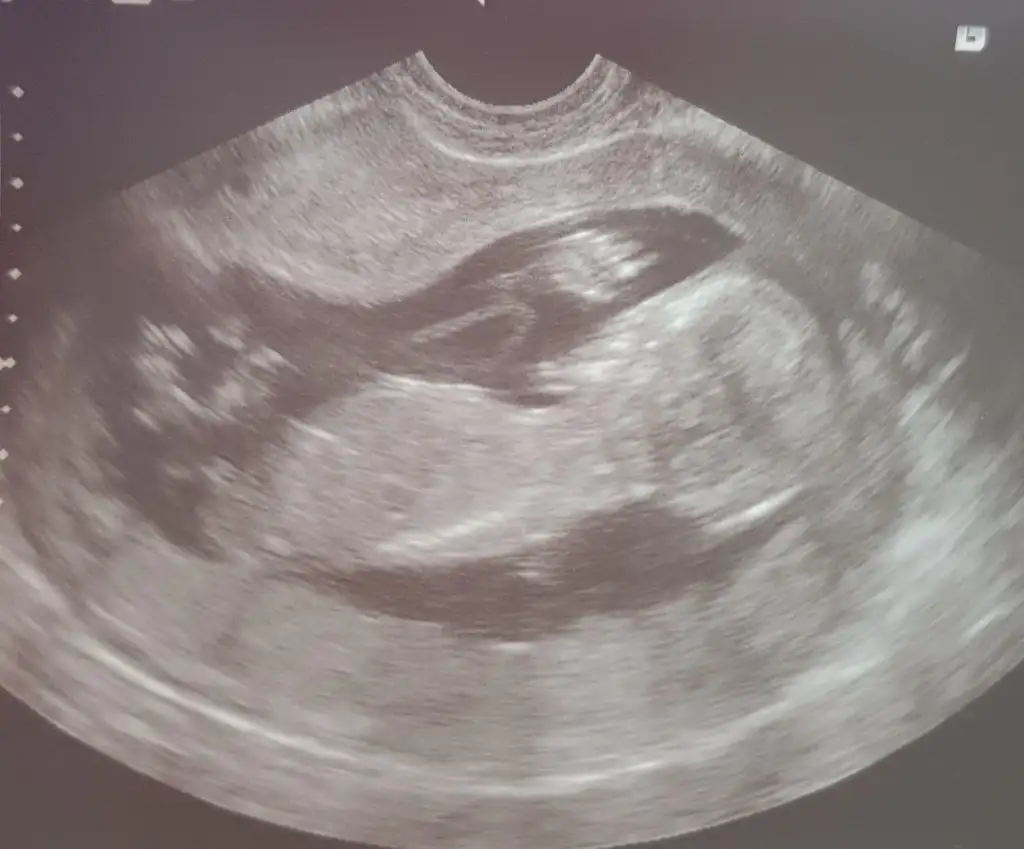

Merhaba yukarıda sanırım arada gözden kaçtı tica etsem banada yorum yaparmısınız 12+5 karından usg🤗

• 1D0C3BB0-B487-44F3-B37B-7A476457421F.webp

1D0C3BB0-B487-44F3-B37B-7A476457421F.webp

16,7 KB · Görüntüleme: 70

• 33DFBEE5-3011-4E58-BA24-98457F6D1998.webp

33DFBEE5-3011-4E58-BA24-98457F6D1998.webp

18,3 KB · Görüntüleme: 58

• 593A517D-7442-44A7-9F94-73334677D7C5.webp

593A517D-7442-44A7-9F94-73334677D7C5.webp

17,6 KB · Görüntüleme: 59